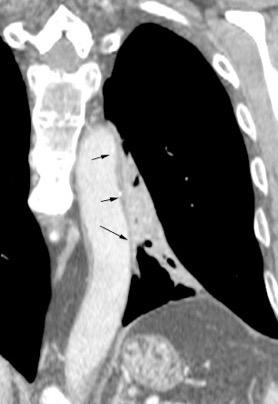

Líneas paraespinales formando un “paréntesis” por encima del diafragma. El signo señala el origen “intratorácico” de la lesión.

Conrad A et al. Pott’s disease associated with large and multiple abscesses in a 30-year-old migrant from Chad. BMJ Case Rep 2018

(lesiones toracoabdominales) La divergencia de las líneas paraespinales apunta a lesión toracoabdominal, que desde el tórax desciende y penetra en el abdomen.

Signo del “iceberg” positivo en Tb vertebral

Afectación por vía hematógena. Región dorsolumbar más frecuente. Afectación inicial: irregularidad de los platillos vertebrales, disminución del disco intervertebral con esclerosis ósea adyacente. Kim. Radiographics.2001